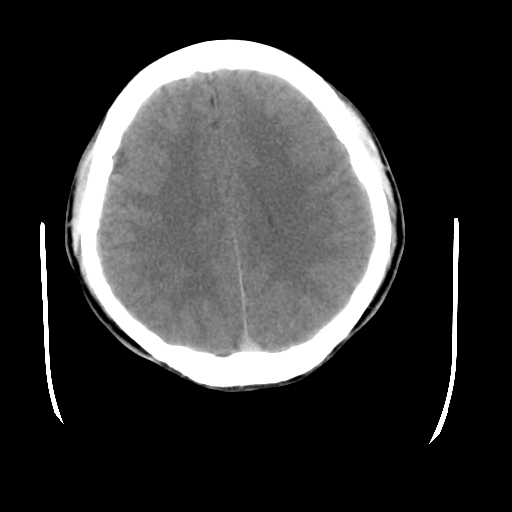

标题: CT23601:男, 17岁,剧烈头痛一小时。 [打印本页]

标题: CT23601:男, 17岁,剧烈头痛一小时。

男, 17岁,剧烈头痛一小时。

颅脑ct轴位平扫颅内未见明确异常;建议:必要时复查。